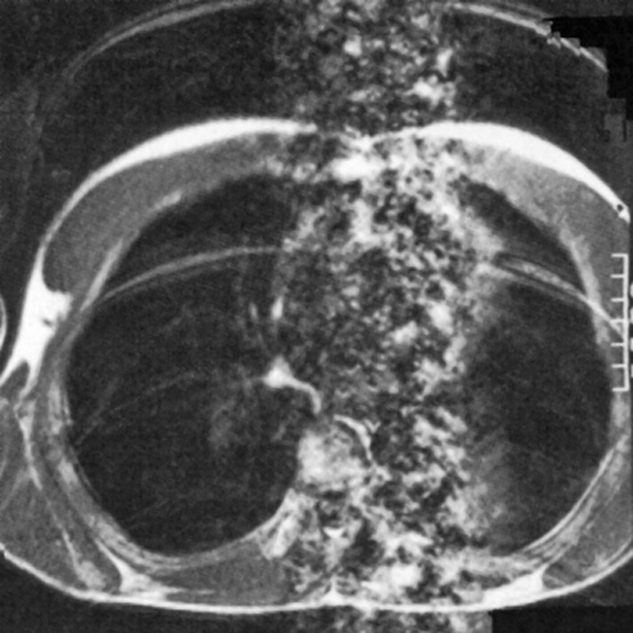

Figure 17-07:

Ghost images resulting from respiratory and cardiac motion with both sets of ar­ti­facts being oriented along the phase en­cod­ing gradient. The respiratory motion produces a number of distinct ghost ima­ges of the chest wall, while the cardiac mo­tion results in the column of noise as­so­cia­ted with the heart.